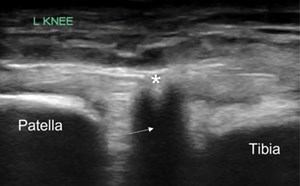

Advanced Echo Pocket Card Series #2: Diastolic Dysfunction

69-year old male with history of hypertension, diabetes, squamous cell carcinoma of larynx status post chemotherapy, radiation, total laryngectomy, tracheostomy dependence, and status post renal trans...